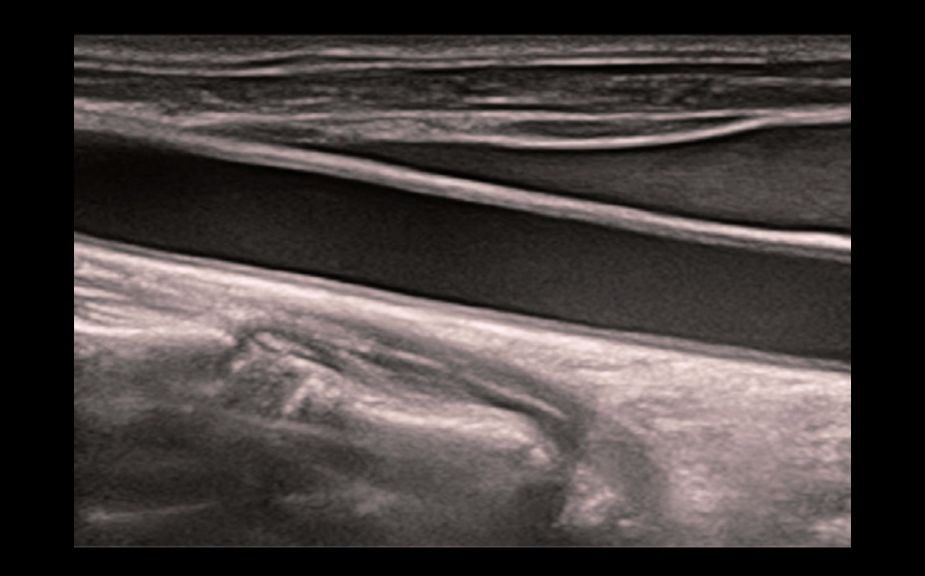

Diagnostyka zmian ogniskowych za pomoc? obrazowania ze ?rodkiem kontrastowym UWN+

Wykorzystanie zar├│wno sygna?├│w drugiej harmonicznej oraz nieliniowych sygna?├│w podstawowych

Wi?ksza czu?o?? w przypadku s?abszych sygna?├│w i d?u?szy czas dzia?ania ?rodka przy ni?szym MI

CEUS - nowotw├│r w?troby z przerzutami

CEUS - perfuzja w gruczolaku tarczycy